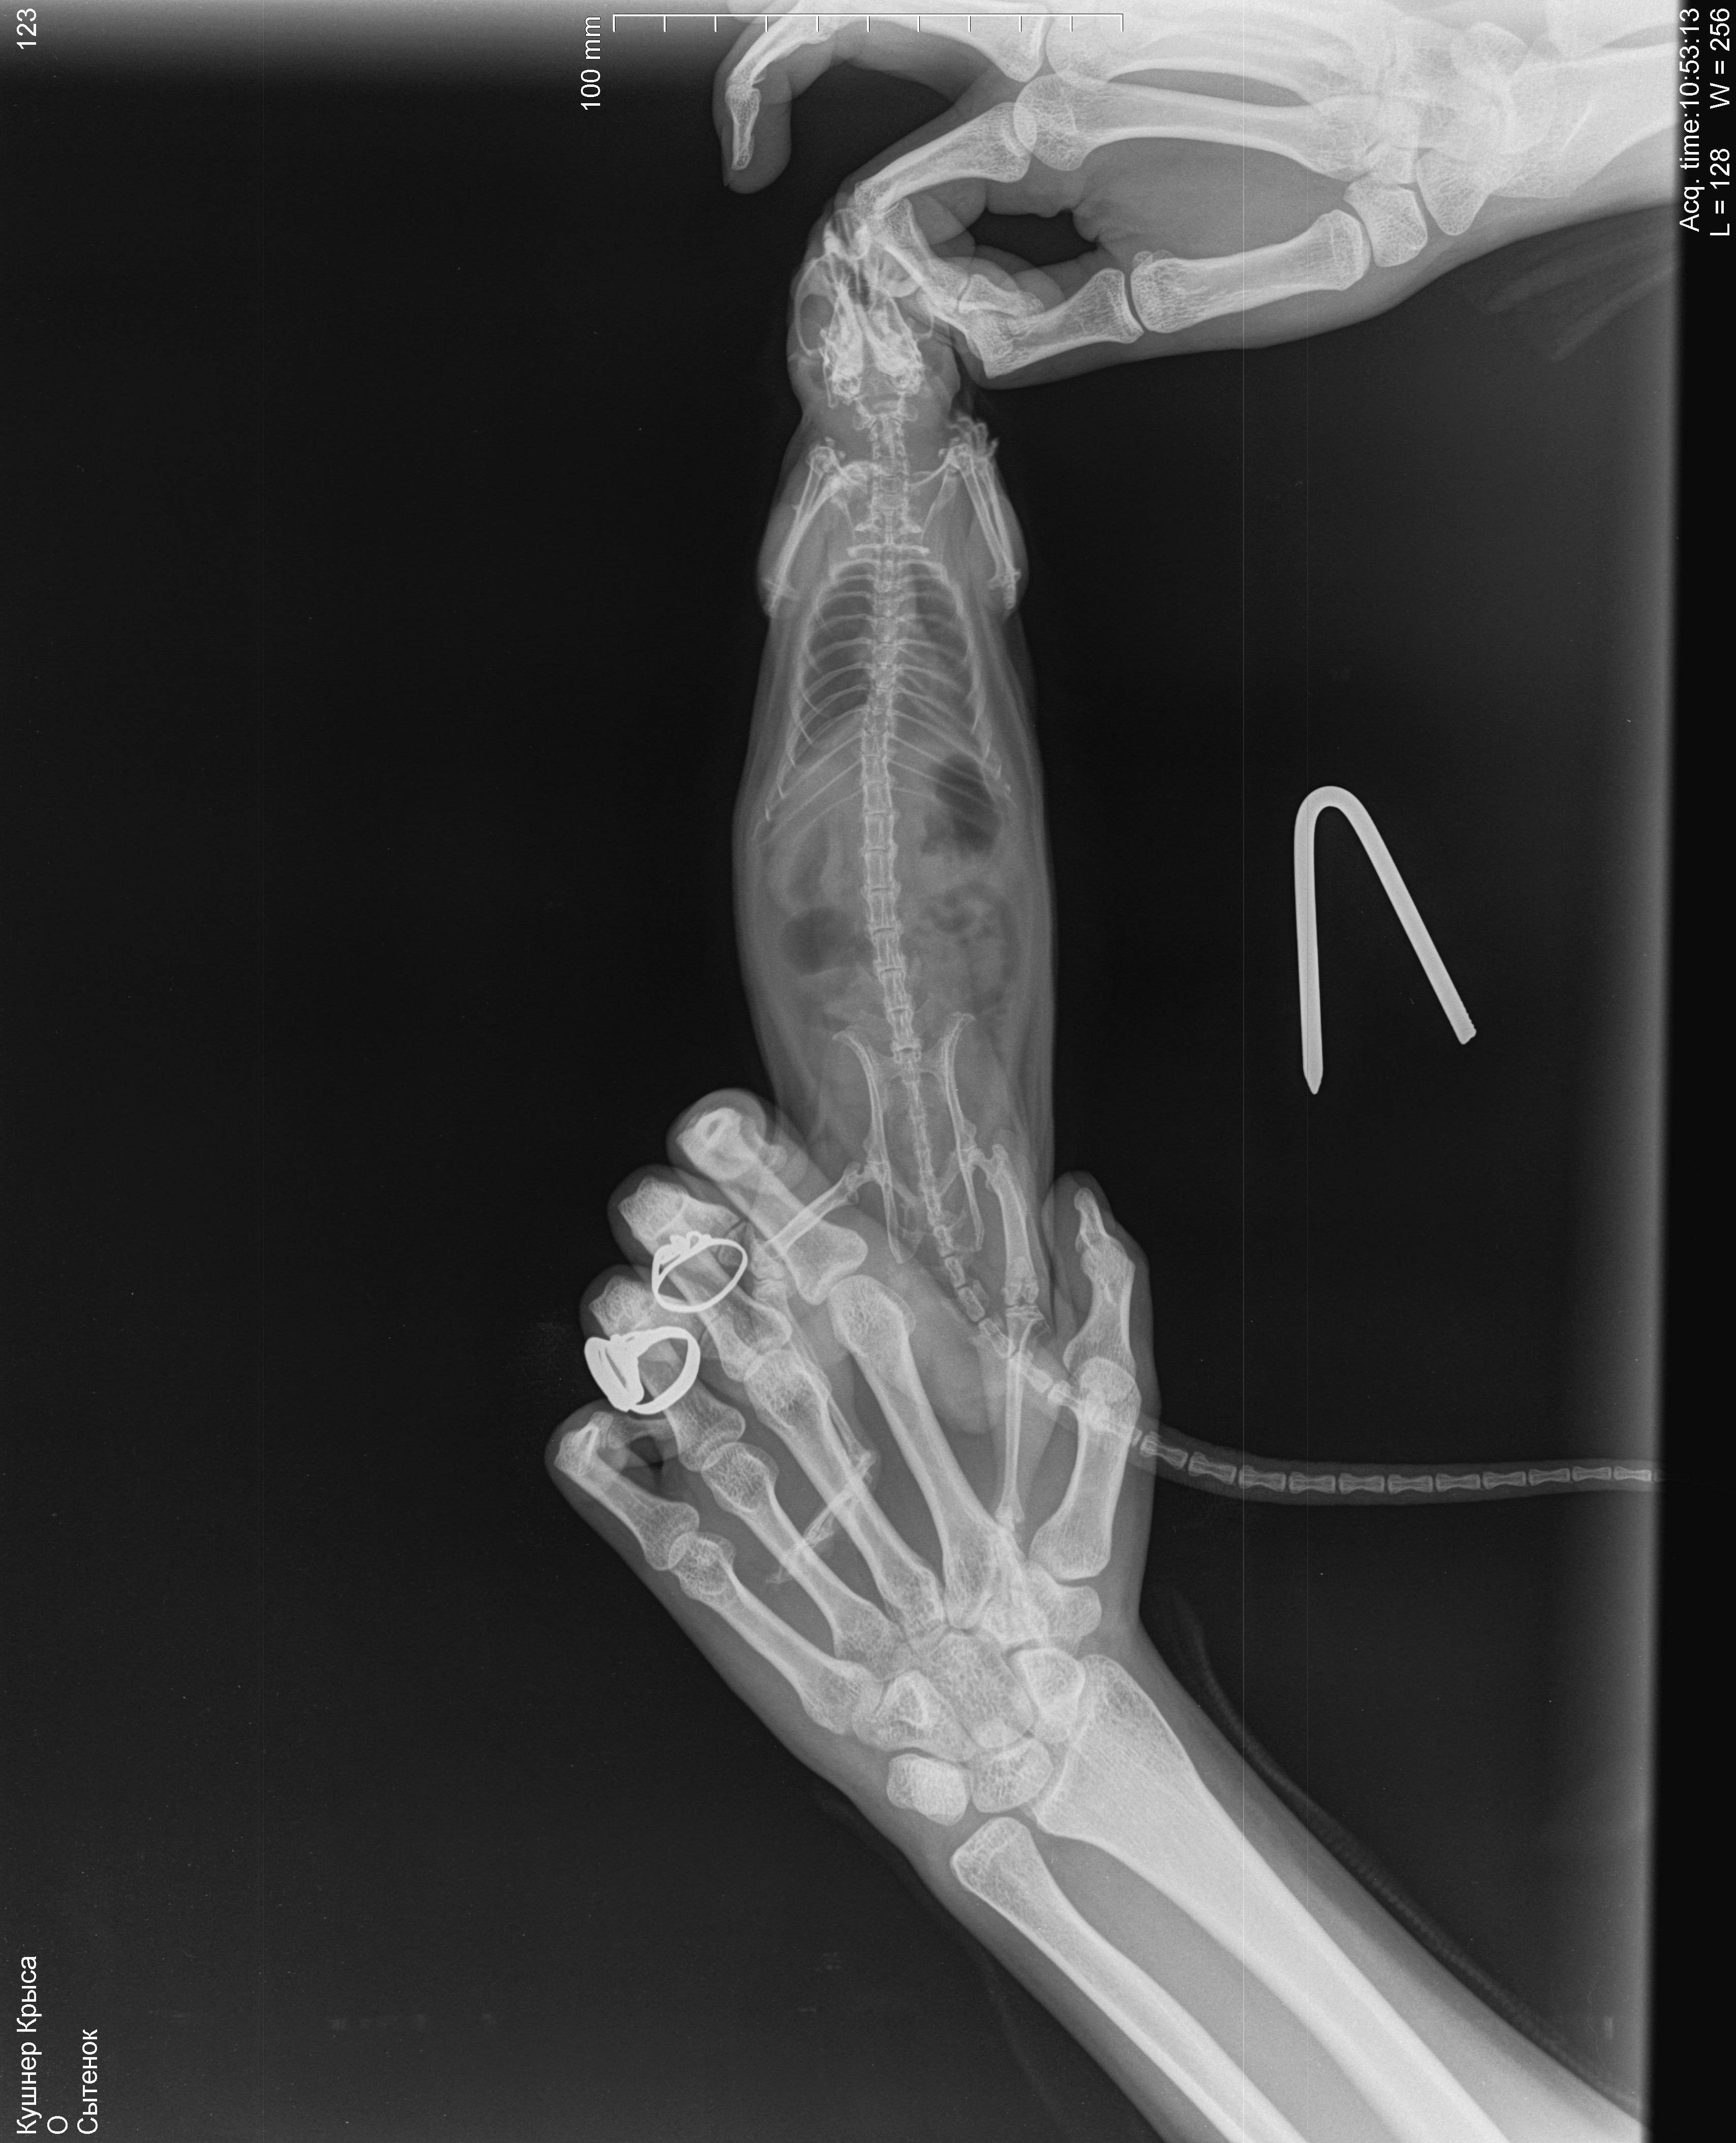

6 декабря свозила к ветеринару, послушали - услышали хрипы, больше слева, сделали рентген, врач сказала, что вероятнее всего пневмония, назначила синулокс 0,15мл в/м 1 раз в день, катозал 0,3мл 1 раз в день. По-моему стало немного получше, начал умываться. Дома пару раз пытался попить, но такое ощущение, словно захлебываться начинает и перестает, стал незначительно активнее. 8,9 декабря возила его на оксигенотерапию по 1 разу по 20минут, в состоянии особо изменения не заметила. 10 числа ближе к вечеру - крыса сидит на одном место, тяжело дышит, дышит боками, хрипы более выраженные, голова опущена вниз, беспокойный, в руки не дается. Повезла к другому врачу (рабочее время моего закончилось) - сказал, что вероятнее всего отёк легких, сделал инъекцию дексаметазона 0,05мл в/м. Спросила про диуретики, сказала, что не надо, так как дексаметазон будет выполнять эту функцию в том числе. :/ Отметил, что если не поможет, то наварное ничего уже не поможет. Сегодня, 11 числа, стало незначительно лучше, поехала к своему врачу, она была на выезде, приняла другая девушка, сказала что не отёк, т.к. хрипы должны быть другие. Назначила ингаляции беродуала и соответственно продолжать назначенную терапию.

Я не знаю, продолжать ли терапию, или её стоит поменять или я только мучаю крысу и ей врят ли уже помогут. Есть ли смысл покупать беродуал? Посмотрите на снимки, пожалуйста, действительно ли пневмония, а не онко? В прямой проекции видно затемнение в проекции шейных позвонков, но на боковой его не вижу, врачи сказали, что это надгортанник ](*,) , хочется быть уверенной, что не какое-нибудь инородное тело.

Кушнер Крыса_DX_20181206_105313_1.jpg